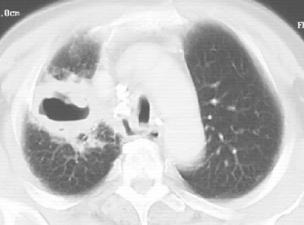

图1-1 男性,32岁,干咳发热1个月,急性血行播散型肺结核

(2)血行播散型肺结核:本型是各型肺结核中较严重者,是急性全身血行播散型结核病的一部分;多由原发型肺结核发展而来,但成年人大多由肺外结核病灶破溃至血管所引起。本病起病急,有全身毒血症状,常伴有结核性脑膜炎;X线显示双肺在浓密的网状阴影上满布境界清晰的粟粒状阴影,直径约2mm,大小及密度均大体相等(图1-1)。病初胸部X线表现可能无明显粟粒状影,或仅有弥漫性网状改变,易误诊为伤寒、败血症等其他发热性疾病。若人体抵抗力较强,少量结核菌分批经血液循环进入肺部,则血行播散灶常大小不均、新旧不等,在双肺上中部呈对称性分布,称为亚急性或慢性血行播散型肺结核。其病情发展缓慢,通常无显着中毒症状。患者可无自觉症状,偶于X线检查时才被发现。此时病灶多较稳定或已硬结愈合。